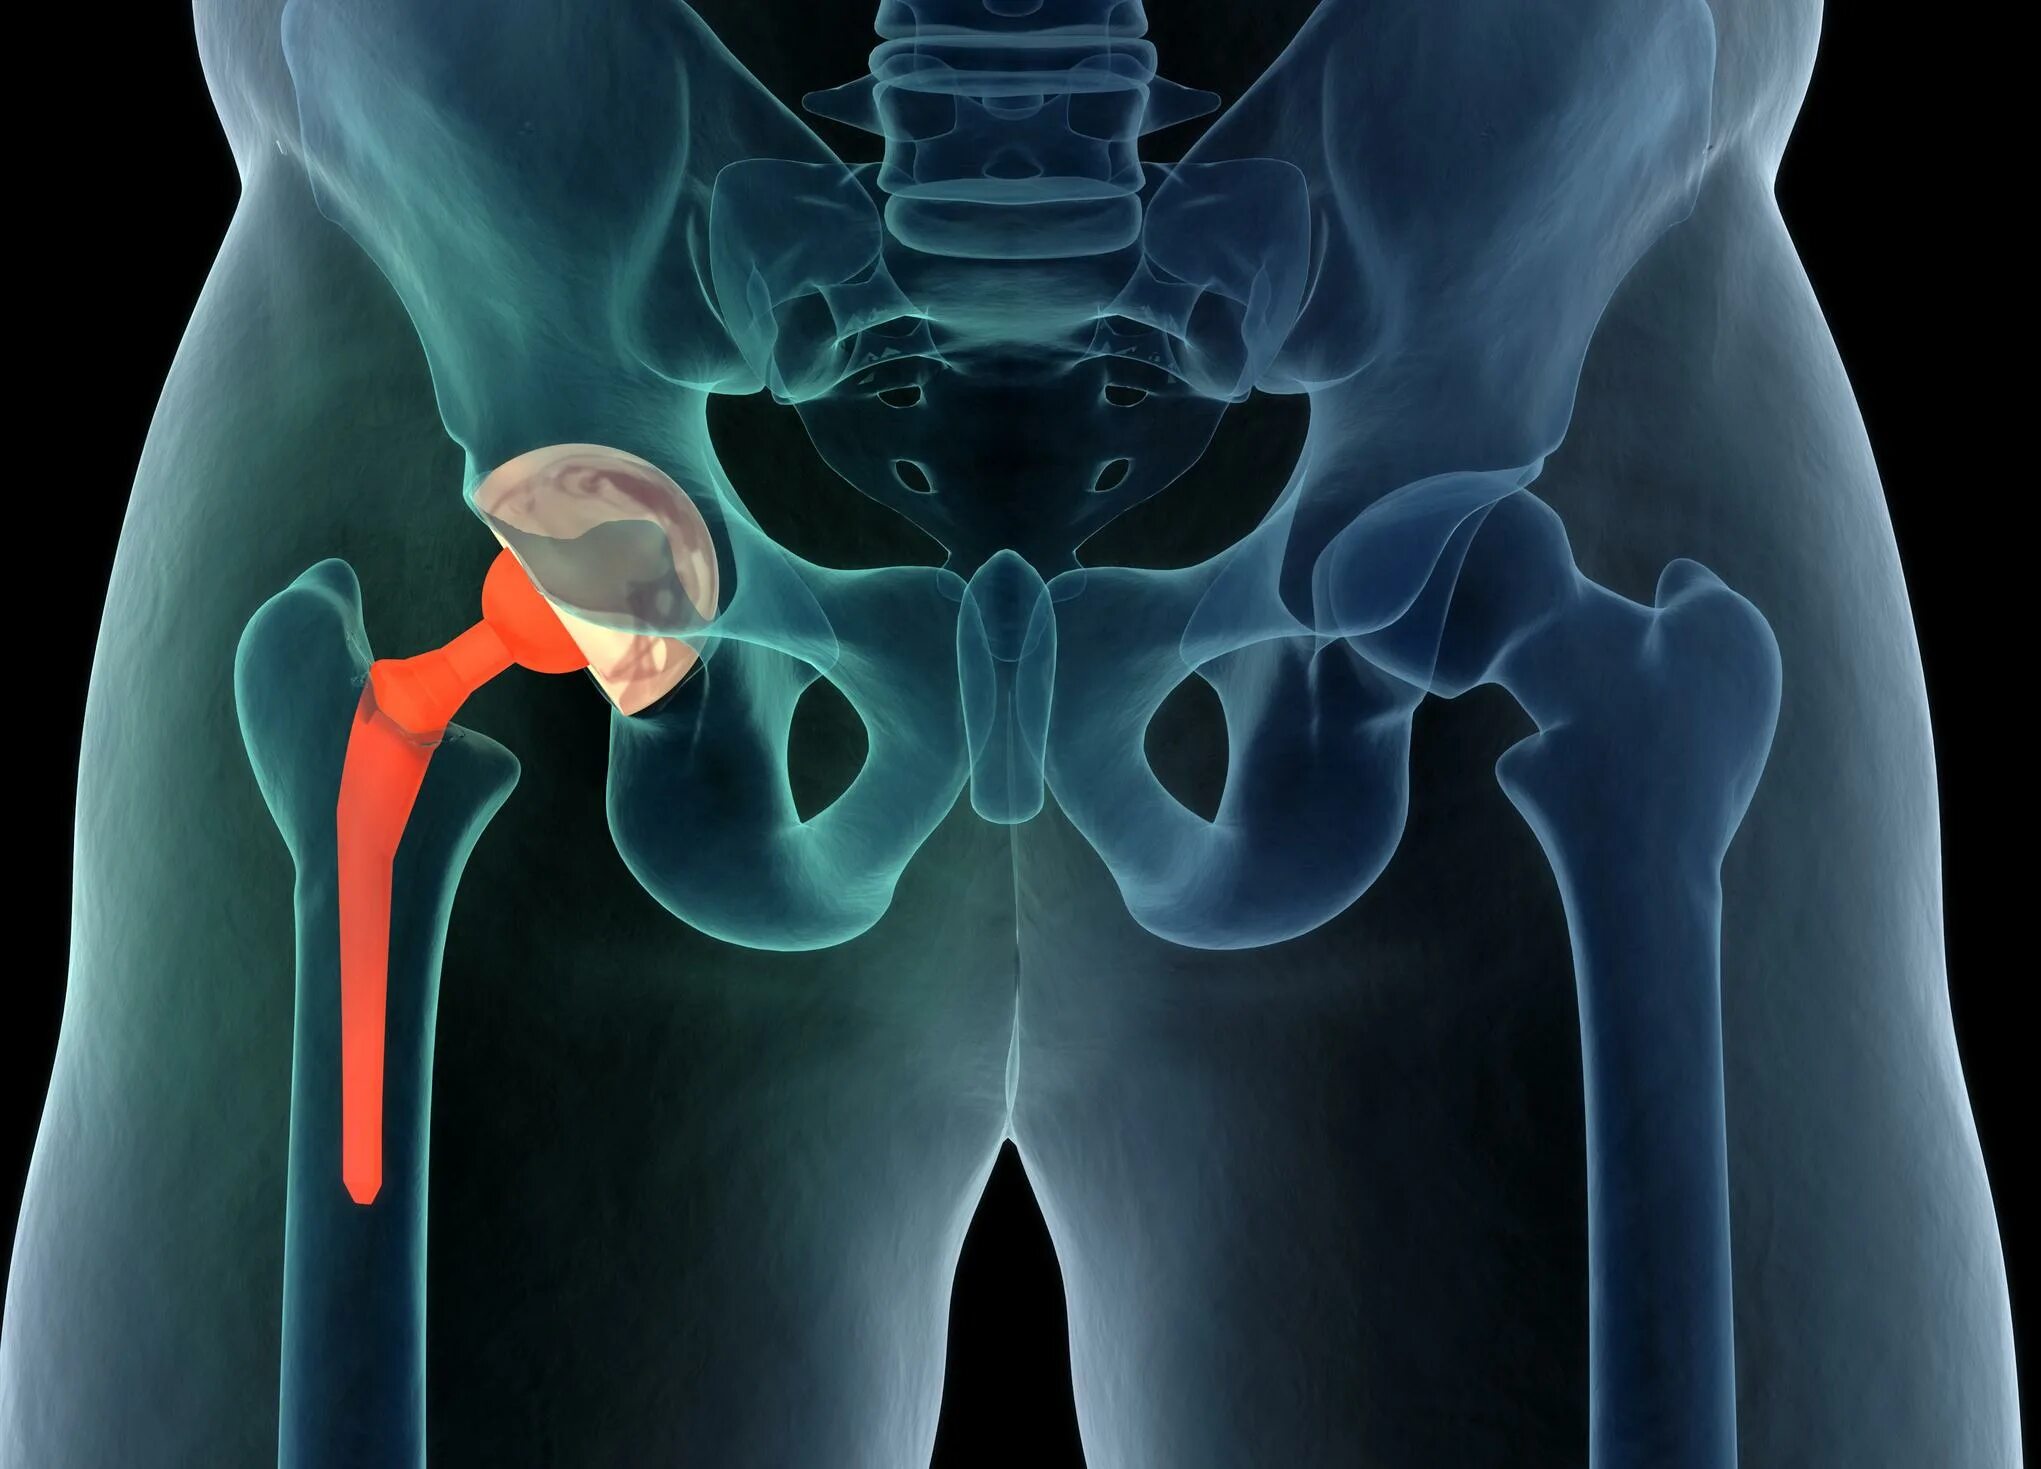

Тазобедренный сустав это